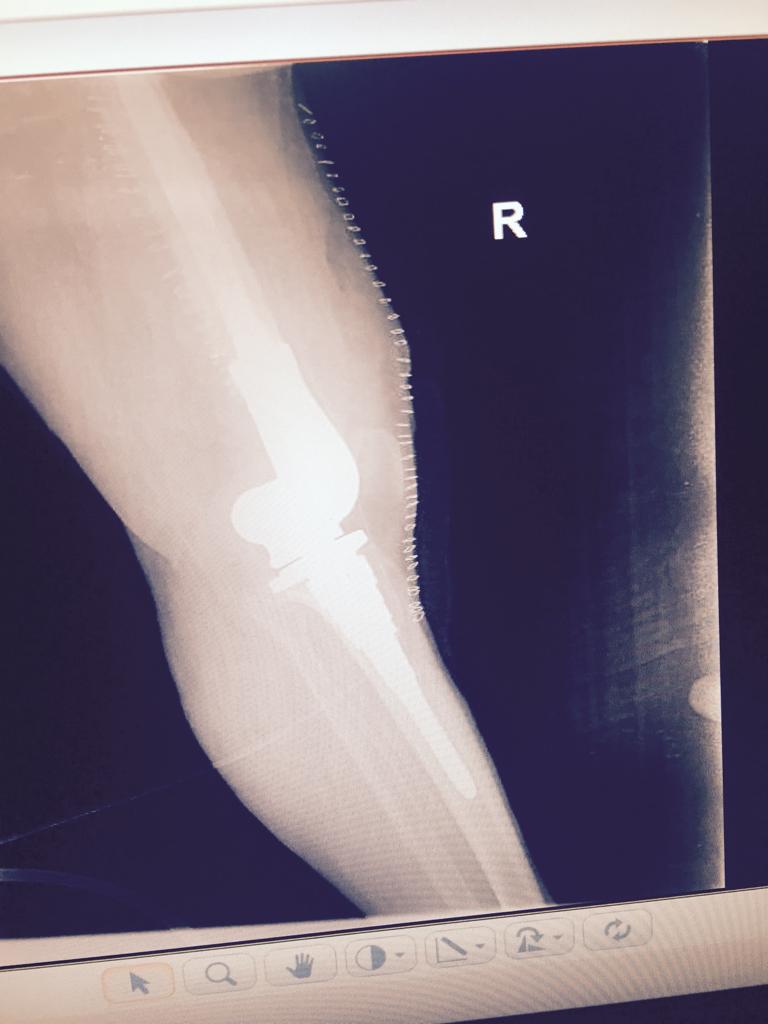

Total Knee Arthroplasty After a non-union